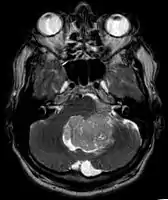

An ependymoma is a tumor that arises from the ependyma, a tissue of the central nervous system. Usually, in pediatric cases the location is intracranial, while in adults it is spinal. The common location of intracranial ependymomas is the fourth ventricle. Rarely, ependymomas can occur in the pelvic cavity.

Ependymomas make up about 5% of adult intracranial gliomas and up to 10% of childhood tumors of the central nervous system (CNS). Their occurrence seems to peak at age 5 years and then again at age 35. They develop from cells that line both the hollow cavities of the brain and the canal containing the spinal cord, but they usually arise from the floor of the fourth ventricle, situated in the lower back portion of the brain, where they may produce headache, nausea and vomiting by obstructing the flow of cerebrospinal fluid. This obstruction may also cause hydrocephalus. They may also arise in the spinal cord, conus medullaris and supratentorial locations.[4] Other symptoms can include (but are not limited to): loss of appetite, difficulty sleeping, temporary inability to distinguish colors, uncontrollable twitching, seeing vertical or horizontal lines when in bright light, and temporary memory loss. It should be remembered that these symptoms also are prevalent in many other illnesses not associated with ependymoma.

Although some ependymomas are of a more anaplastic and malignant type, most of them are not anaplastic. Well-differentiated ependymomas are usually treated with surgery. For other ependymomas, total surgical removal is the preferred treatment in addition to radiation therapy. The malignant (anaplastic) varieties of this tumor, malignant ependymoma and the ependymoblastoma, are treated similarly to medulloblastoma but the prognosis is much less favorable. Malignant ependymomas may be treated with a combination of radiation therapy and chemotherapy. Ependymoblastomas, which occur in infants and children younger than 5 years of age, may spread through the cerebrospinal fluid and usually require radiation therapy. The subependymoma, a variant of the ependymoma, is apt to arise in the fourth ventricle but may occur in the septum pellucidum and the cervical spinal cord. It usually affects people over 40 years of age and more often affects men than women.[7]